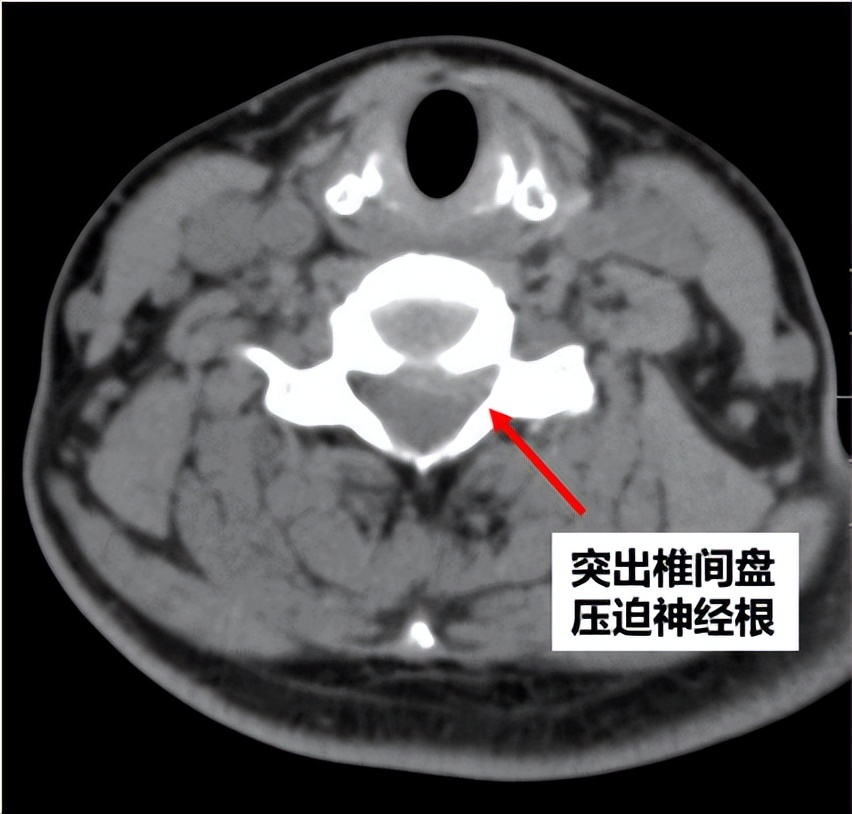

为明确诊断,卢祺主治医师为患者安排了颈椎CT和MRI检查。影像结果提示患者颈5/6节段存在椎间盘突出,压迫左边的神经根,导致患者颈肩痛、手麻。患者的症状、体征和影像学检查都很典型,符合神经根型颈椎病的诊断。